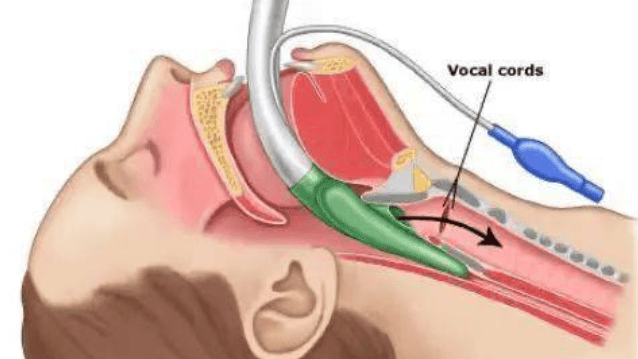

咽喉手术

针对咽喉部位病变:如扁桃体&腺样体切除术、声带息肉切除术、会厌囊肿切除术等。

声导息肉治疗成果展示